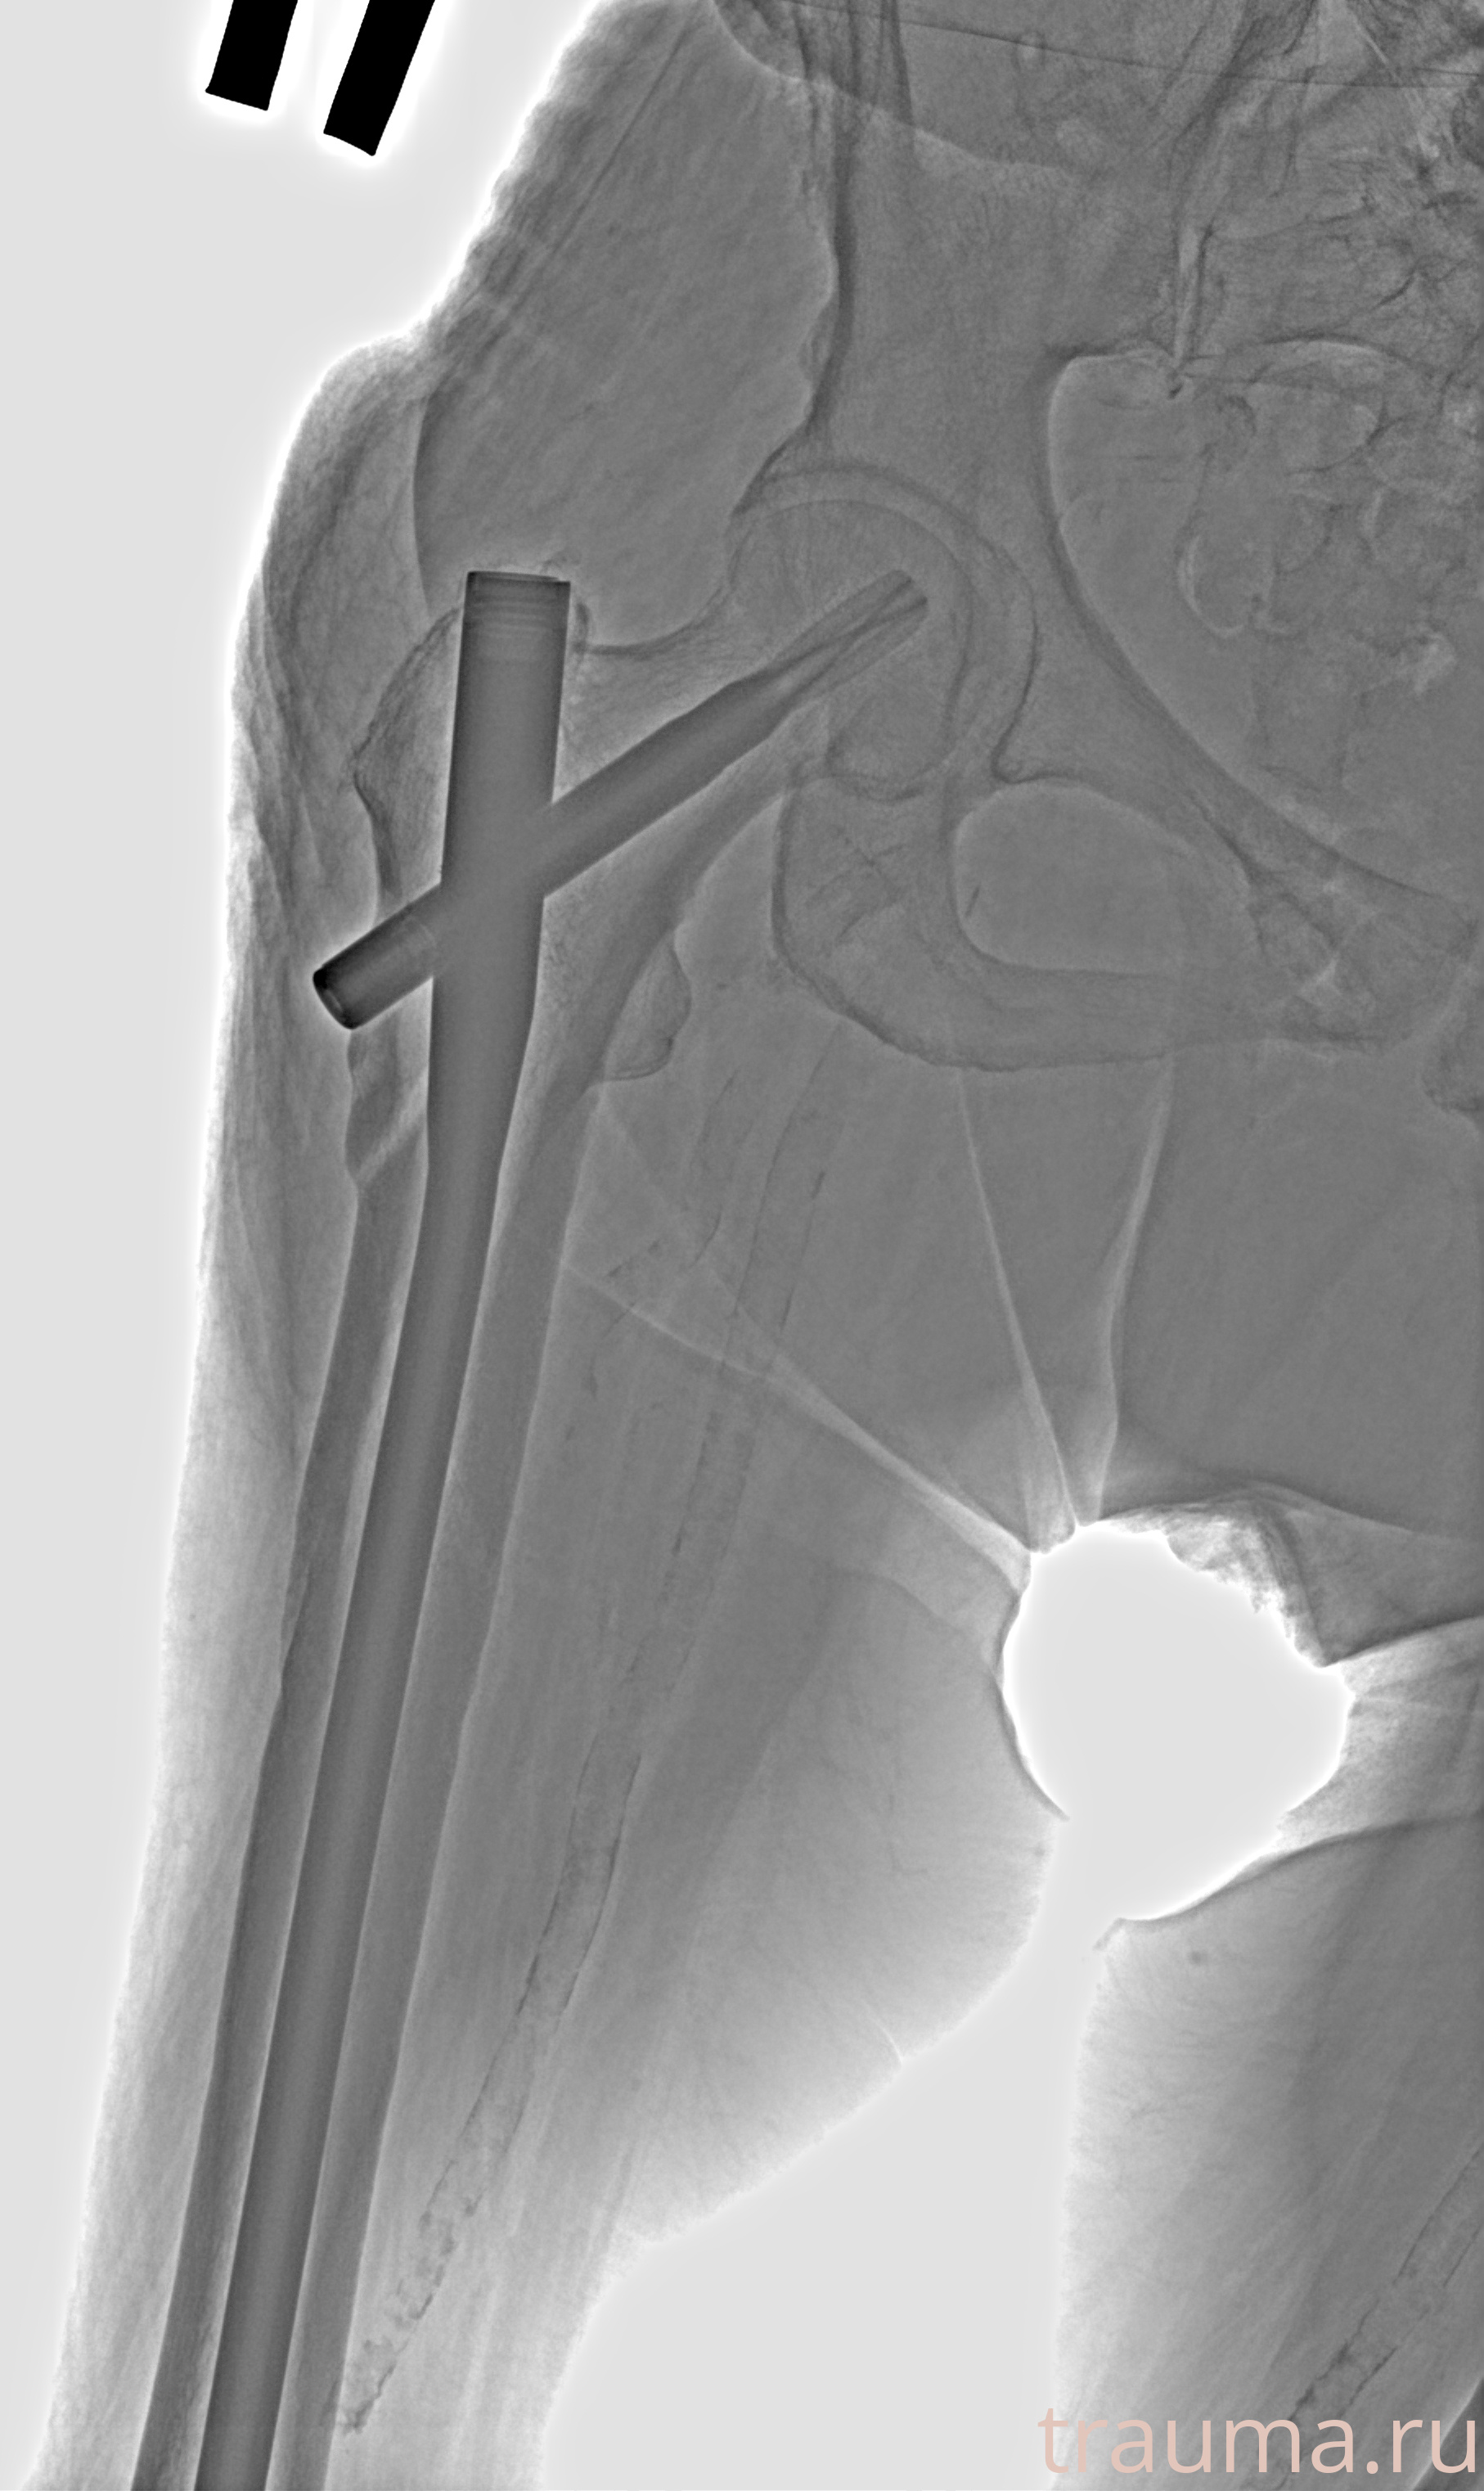

Рентгенограммы

Рентген на дому: по вашему адресу приезжает врач-рентгенолог, травматолог-ортопед с мобильным рентгеновским аппаратом, проводит диагностику травмы или заболевания, делает необходимые рентгенограммы, дает рекомендации по дальнейшему лечению. Получить качественные снимки в домашних условиях возможно благодаря уникальной методике, разработанной МосРентген Центром для института  Склифосовского